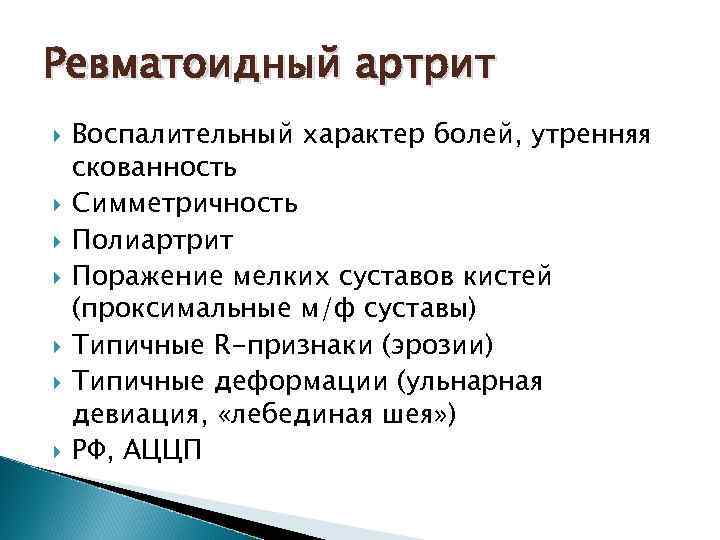

Ревматоидный артрит Воспалительный характер болей, утренняя скованность Симметричность Полиартрит Поражение мелких суставов кистей (проксимальные м/ф суставы) Типичные R-признаки (эрозии) Типичные деформации (ульнарная девиация, «лебединая шея» ) РФ, АЦЦП